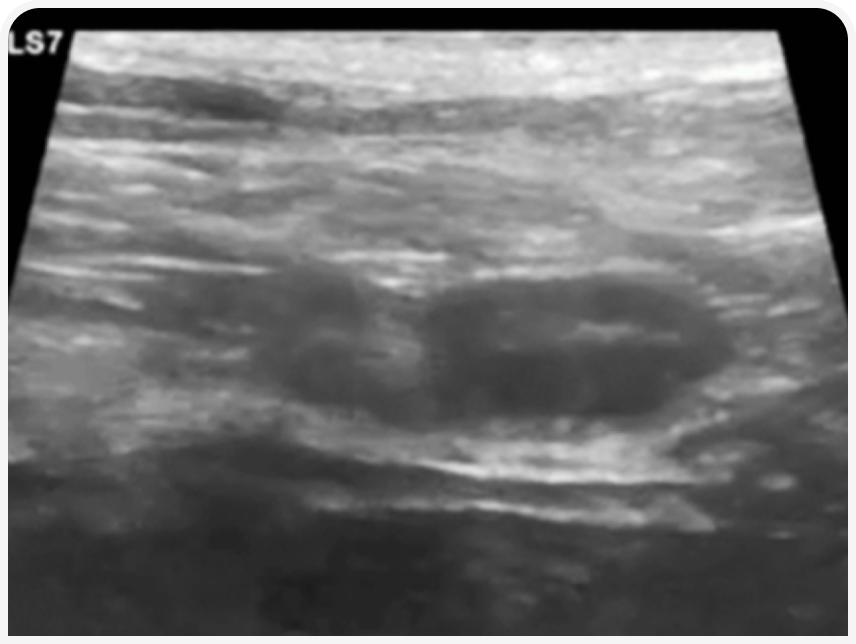

УЗИ в течку будет максимально информативно для определения ОРС. В этот период в корковом слое яичников начинается рост фолликулов, которые у собак около периода овуляции могут достигать размера 1-1,2 см.

При наличии фолликулогенеза яичник приобретает характерную «уникальную» УЗ-картину, что наряду с признаками течки и картиной вагинальной цитологии позволяет подтвердить диагноз ОРС с максимальной достоверностью.

У некоторых животных в реминантном яичнике могут формироваться кисты, вызывающие персистентную течку. Тогда на УЗИ будут обнаружены единичная/множественные кистозные структуры, поликистоз или киста на фоне роста более мелких фолликулов.

У некоторых животных в реминантном яичнике могут формироваться кисты, вызывающие персистентную течку. Тогда на УЗИ будут обнаружены единичная/множественные кистозные структуры, поликистоз или киста на фоне роста более мелких фолликулов. В начале течки яичники могут не иметь хорошо различимых фолликулов. В таком случае стоит повторить исследование через неделю.

Но, как и у сук, в течку яичники будут иметь характерную картину овального образования с множеством кистозных структур размером до 3-4 мм, а культя матки будет утолщаться. Алгоритм проведения исследования аналогичен алгоритму у сук.